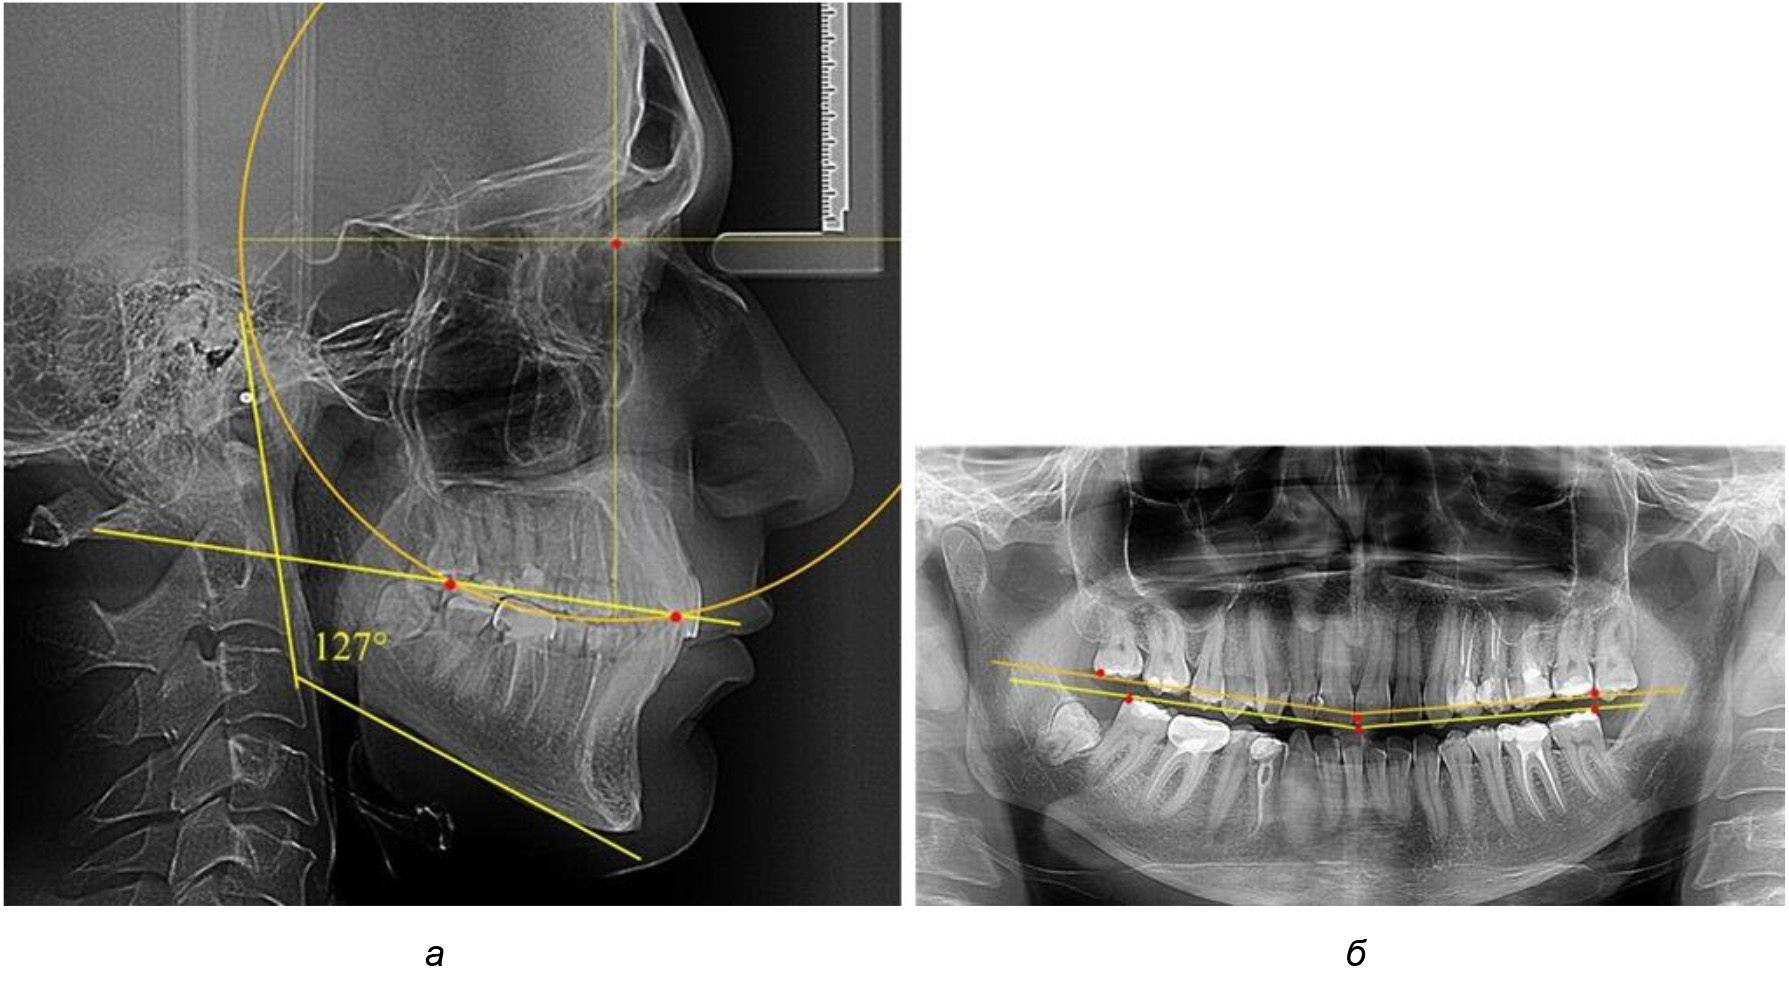

При анализе латеральных ТРГ устанавливали реперный окклюзионные точки в переднем и боковом отделе. Передняя точка устанавливалась на режущем крае нижнего медиального резца, которую в клинике ортодонтии обозначают как vPOcP. Дистальная точка второго нижнего моляра обозначалась как hPOcP. Измеряли расстояние между окклюзионными точками, что определяло сагиттальный размер окклюзионной линии. Использование программ PowerPoint позволило проводить окружность, проходящую по линии смыкания зубов через окклюзионные точки. Измеряли радиус окружности. Учитывая вариабельность размеров окклюзионной линии и радиуса окружности, определяли относительный показатель через отношение радиуса круга к длине сагиттального размера окклюзионной линии. Глубину окклюзионной кривой измеряли от точки наибольшей выпуклости до окклюзионной линии (рис. 1). На ортопантомограмме (ОПТГ) также соединяли окклюзионные точки правой и левой стороны и измеряли глубину окклюзионной кривой от точки наибольшей выпуклости до окклюзионной прямой линии. Результаты глубины кривой Spee сравнивали по данным ТРГ и ОПТГ.

Рис. 1. Метод определения кривой Spee на ТРГ (а) и на ОПТГ (б)

Деление величины радиуса круга к длине окклюзионной линии составило 1,623 ± 0,02. Таким образом, для определения радиуса окружности, соответствующей кривизне окклюзионного контура боковой ТРГ, необходимо измерить расстояние между передней и задней окклюзионными точками и последующим умножением полученной величины на число Фибоначчи (рис. 2).

Рис. 2. Особенности кривой Spee на ТРГ (а) и ОПТГ (б) у людей с признаками вертикального роста